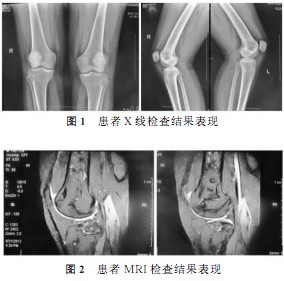

骨梗死早期影像学表现1例

图片尺寸284x281

长期接受激素治疗需警惕膝关节骨坏死

图片尺寸817x1042